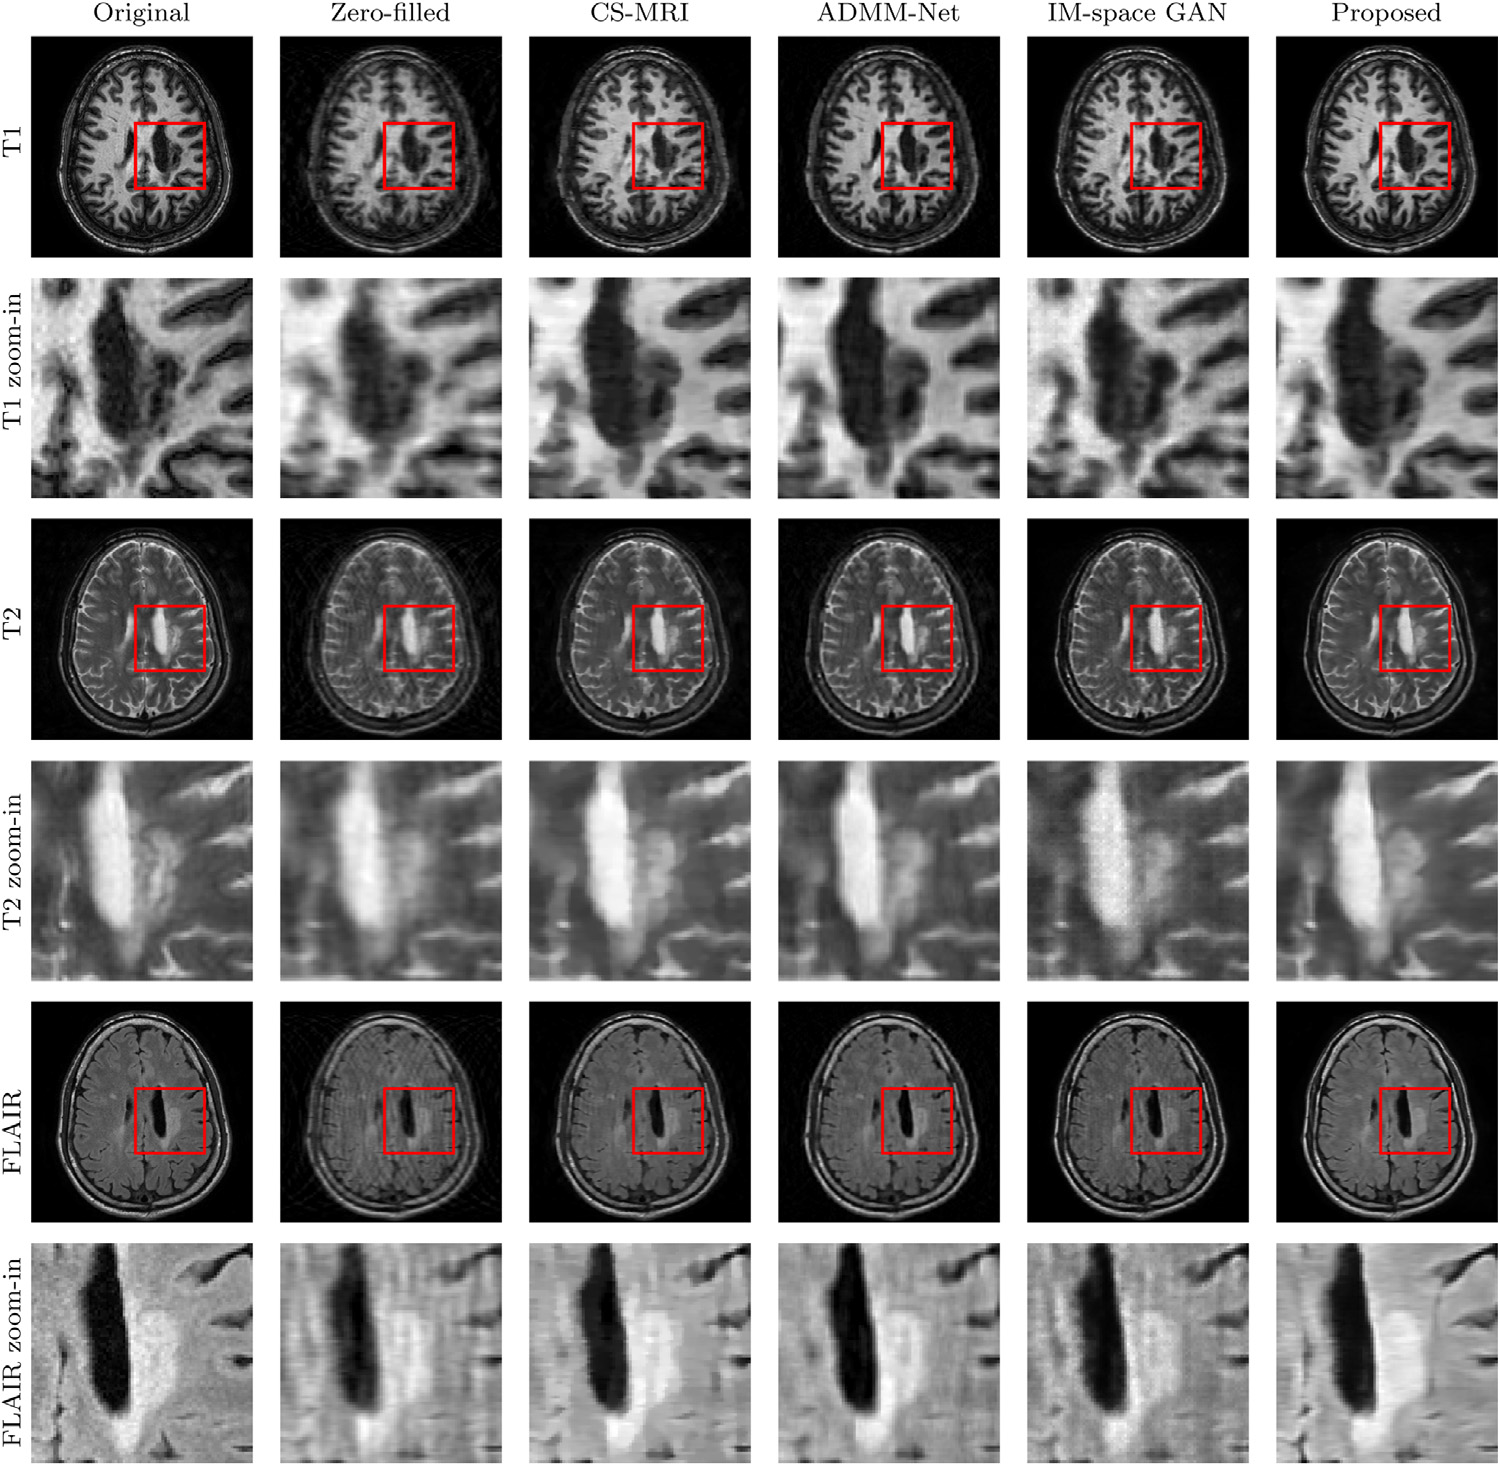

For the IXI dataset, the article provides Figure 2 as visualization of experiment results (sampling rate 20%, that is, only 20% of the original K-space data is used), and provides a quantitative comparison (Table 1 and Table 2) of the whole image using PSNR and SSIM.

Figure 2: Examples of reconstructed MR images from undersampled k-space data using only 20% of the data